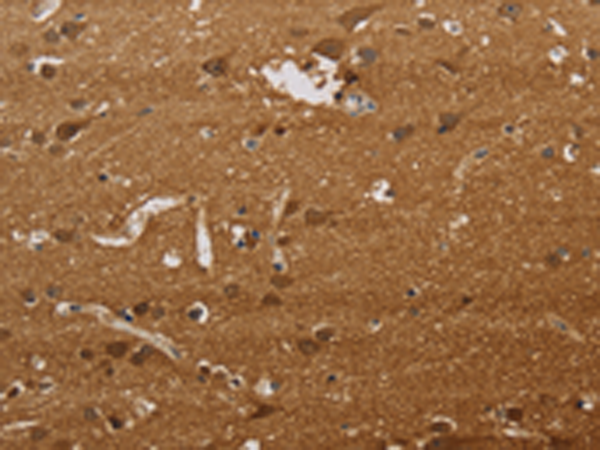

IHC positive control: |

Human brain and Human liver cancer |

IHC Recommend dilution: |

50-200 |